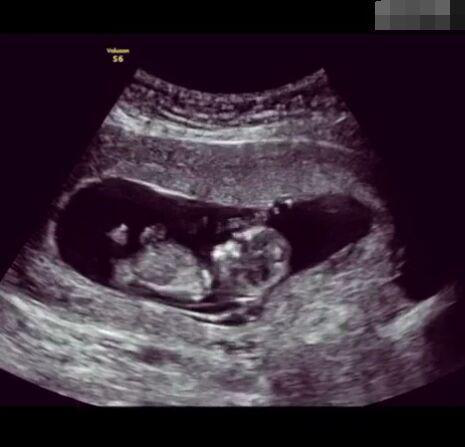

懷孕后,寶寶的性別一直是全家人的重點(diǎn)關(guān)注對象。而男女性別的差異,在基因?qū)用骟w現(xiàn)在第二十三對染色體上,如果是XY則是男孩,XX則是女孩,這都是由那枚與卵子結(jié)合的精子來決定。

圖片8.png

那些做了B超檢查確定胎兒男女,生下來后發(fā)現(xiàn)不對的,多半是因?yàn)樵贐超檢查時(shí)寶寶太調(diào)皮,以致影響了檢查準(zhǔn)確性。就比如說,有的女寶寶在媽媽肚子里玩自己的臍帶,把臍帶夾到了兩腿中間,B超就有一定幾率拍出來好像是男寶寶的特征,導(dǎo)致被誤認(rèn)為是男孩子。還有些男寶寶過分害羞,在做B超時(shí)雙腿緊緊并攏,醫(yī)生也很難判斷男女,只好大致猜測是女孩,就又造成了誤會。因此,B超亦不是萬能的。

其實(shí),不論男女都是父母的乖寶寶,不管是男孩還是女孩,都讓我們一起熱烈歡迎他們的到來吧!